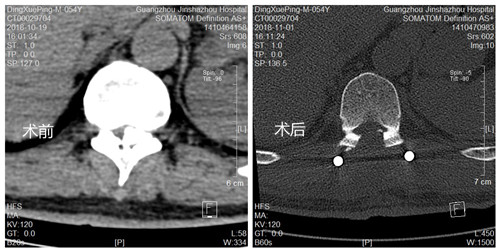

丁叔术前术后CT对比照

经过详细地询问病史和全面的体格检查,CT提示黄韧带骨化,相应胸椎管狭窄。丁叔就是由于胸椎黄韧带骨化,压迫胸髓引起左下肢痉挛性瘫痪,左下肢僵硬、活动不便、偏瘫步态,严重影响日常生活。

骨科中心郑主任精心为丁叔制定了详细的手术方案,做好了充分的术前准备,降低了手术风险,使得丁叔的手术顺利完成,术后左下肢肌张力明显下降,肢体活动灵活、行走步态明显改善,临床治疗效果佳,经过几天的康复锻炼和功能训练,现在丁叔已康复出院、平安归家。